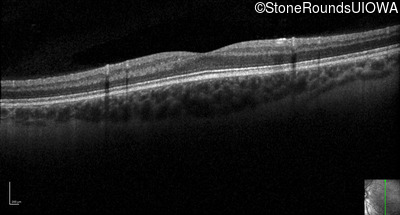

Optical Coherence Tomography - Left - 10/200 sc

Exemplar / OCT Stack

OCT Stack